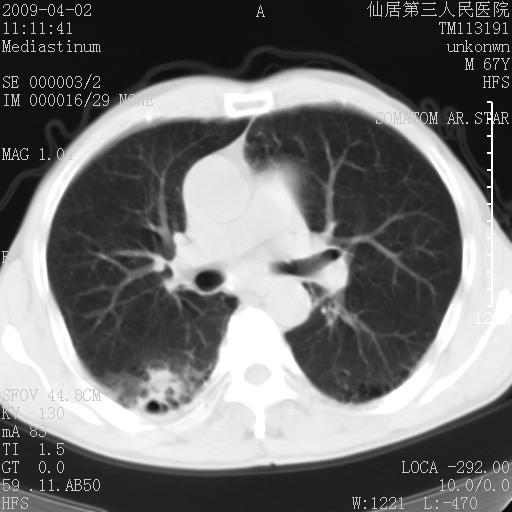

患者老年男性,乏力畏寒来诊,摄胸片示右下肺感染性病变,抗炎两周后复查胸片,无好转有进展。

后做ct平扫表现如下:

考虑右肺炎症可能性大,不除外细支气管肺泡癌

是否还要考虑肺间质纤维化,建议hrct扫描。

病灶呈蜂窝征,纵隔多个淋巴结肿大;肺泡癌需考虑

右肺下叶背段干酪性肺炎。请痰检[emb28]

我认为普通的感染应该可以除外,间质性肺炎可能性较大,但如何解释纵膈的淋巴结肿大呢

考虑双肺间质性改变(间质纤维化?)伴右肺下叶感染。